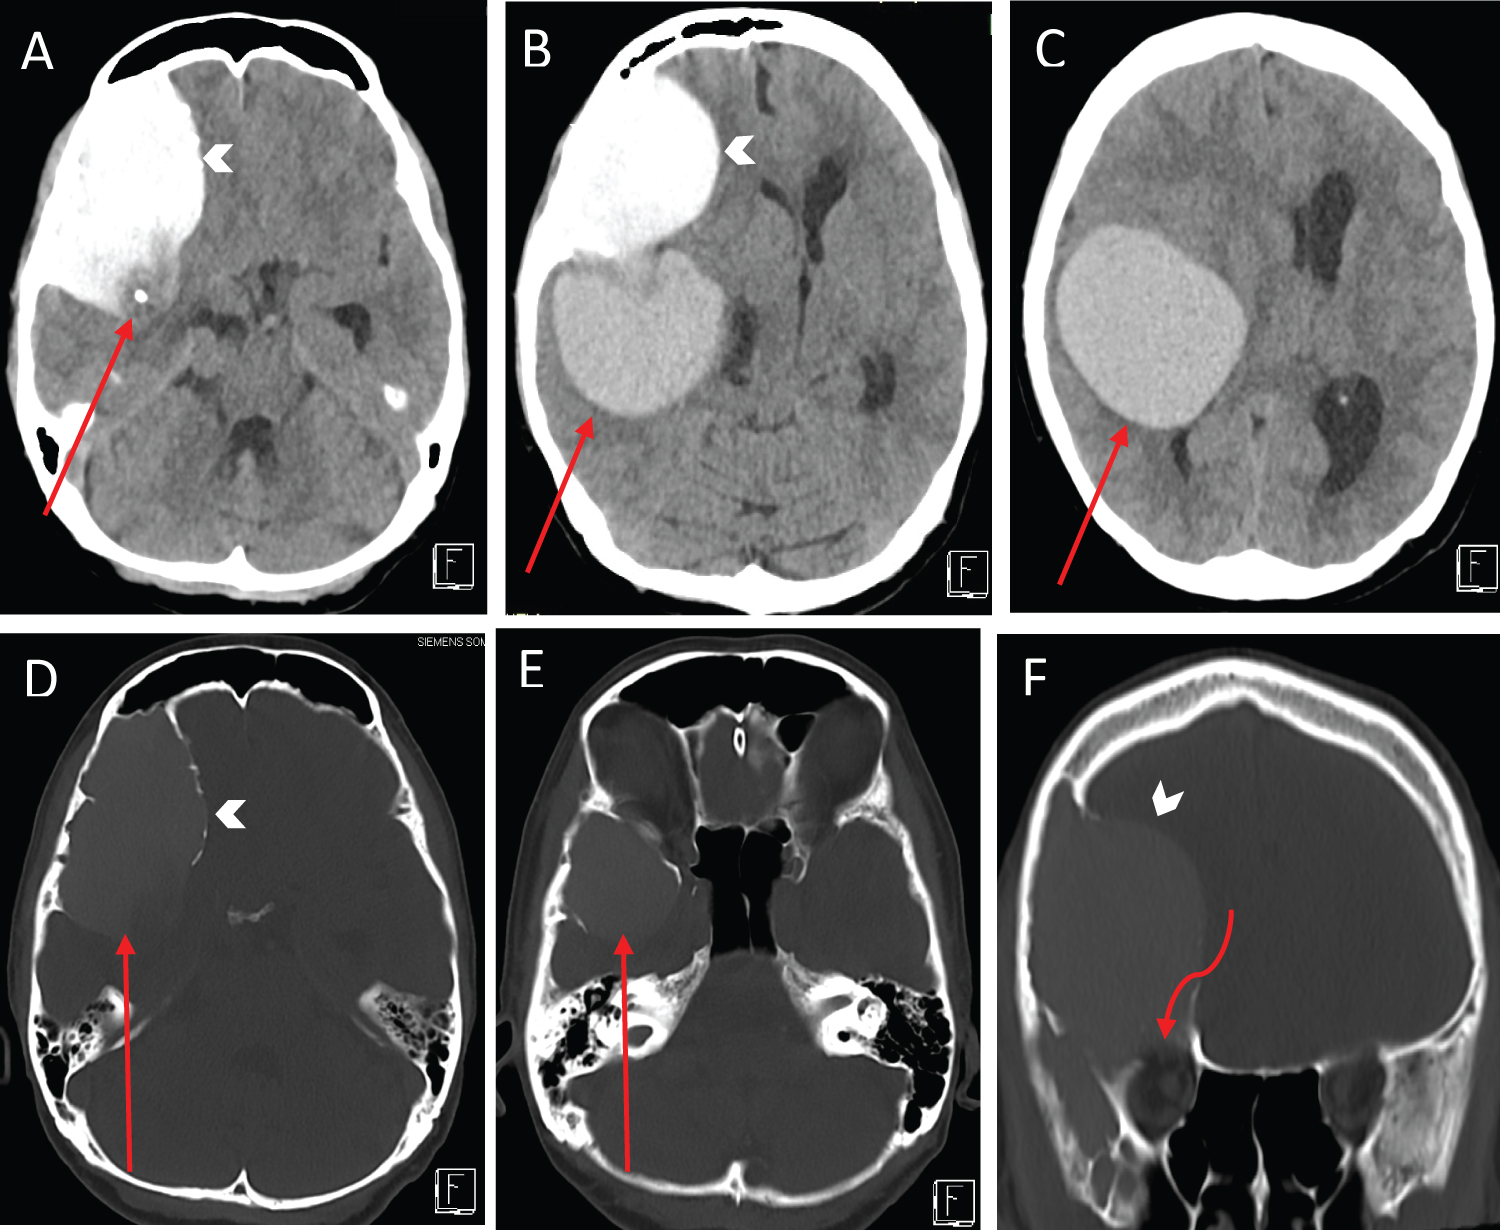

Computed tomography (CT) scan of the brain at the emergency department showed a markedly hyperdense right frontotemporal intradiploic lesion with scalloping of the overlying skull vault and orbital roof, as well as a large right intraparenchymal lesion just adjacent to the Sylvian fissure (Figure 1). Subsequent MRI revealed two large discrete masses containing varying proteinaceous content (Figure 2). The anterior extra-axial lesion measured 6.8 × 4.4 × 4.2 cm, occupying the right anterior and middle cranial fossae, and expanding the greater wing of the right sphenoid bone. It was hyperintense on T1-weighted imaging, hypointense on T2-weighted imaging with susceptibility changes secondary to internal calcifications. The posterior lesion measured 5.1 × 4.6 × 5.8 cm and demonstrated isointensity on T2-weighted and hyperintensity on T1-weighted sequences. Located in the right extra-axial temporal region and posterior to the Sylvian fissure, the lesion resulted in radial displacement of the underlying brain parenchyma. Both lesions did not show any post-contrast enhancement nor restricted diffusion. There was significant mass effect on the right frontotemporal lobes with mild perilesional oedema and leftward midline shift. There was effacement of the right lateral ventricle, with subfalcine and transtentorial herniations.

Figure 1: Axial non-contrast computed tomography (CT) head images (A-E) show a markedly hyperdense intradiploic lesion (arrow heads) scalloping the outer and inner tables of the right fronto temporal skull vault (D-E). There is a large hyperdense intraparenchymal lesion in the right frontal and temporal lobes (red arrows, in B and C). There is close contact between the intradiploic and intraparenchymal lesions (red arrows, D and E) with focal calcification at the junction between them (red arrow, A). The lesions cause significant mass effect with leftward shift of the midline structures and effacement of the right lateral ventricle. Coronal non-contrast CT head image (F) shows thinning of the inner table of the right frontal skull vault including the right anterior cranial fossa and the orbital roof (curved arrow). View Figure 1